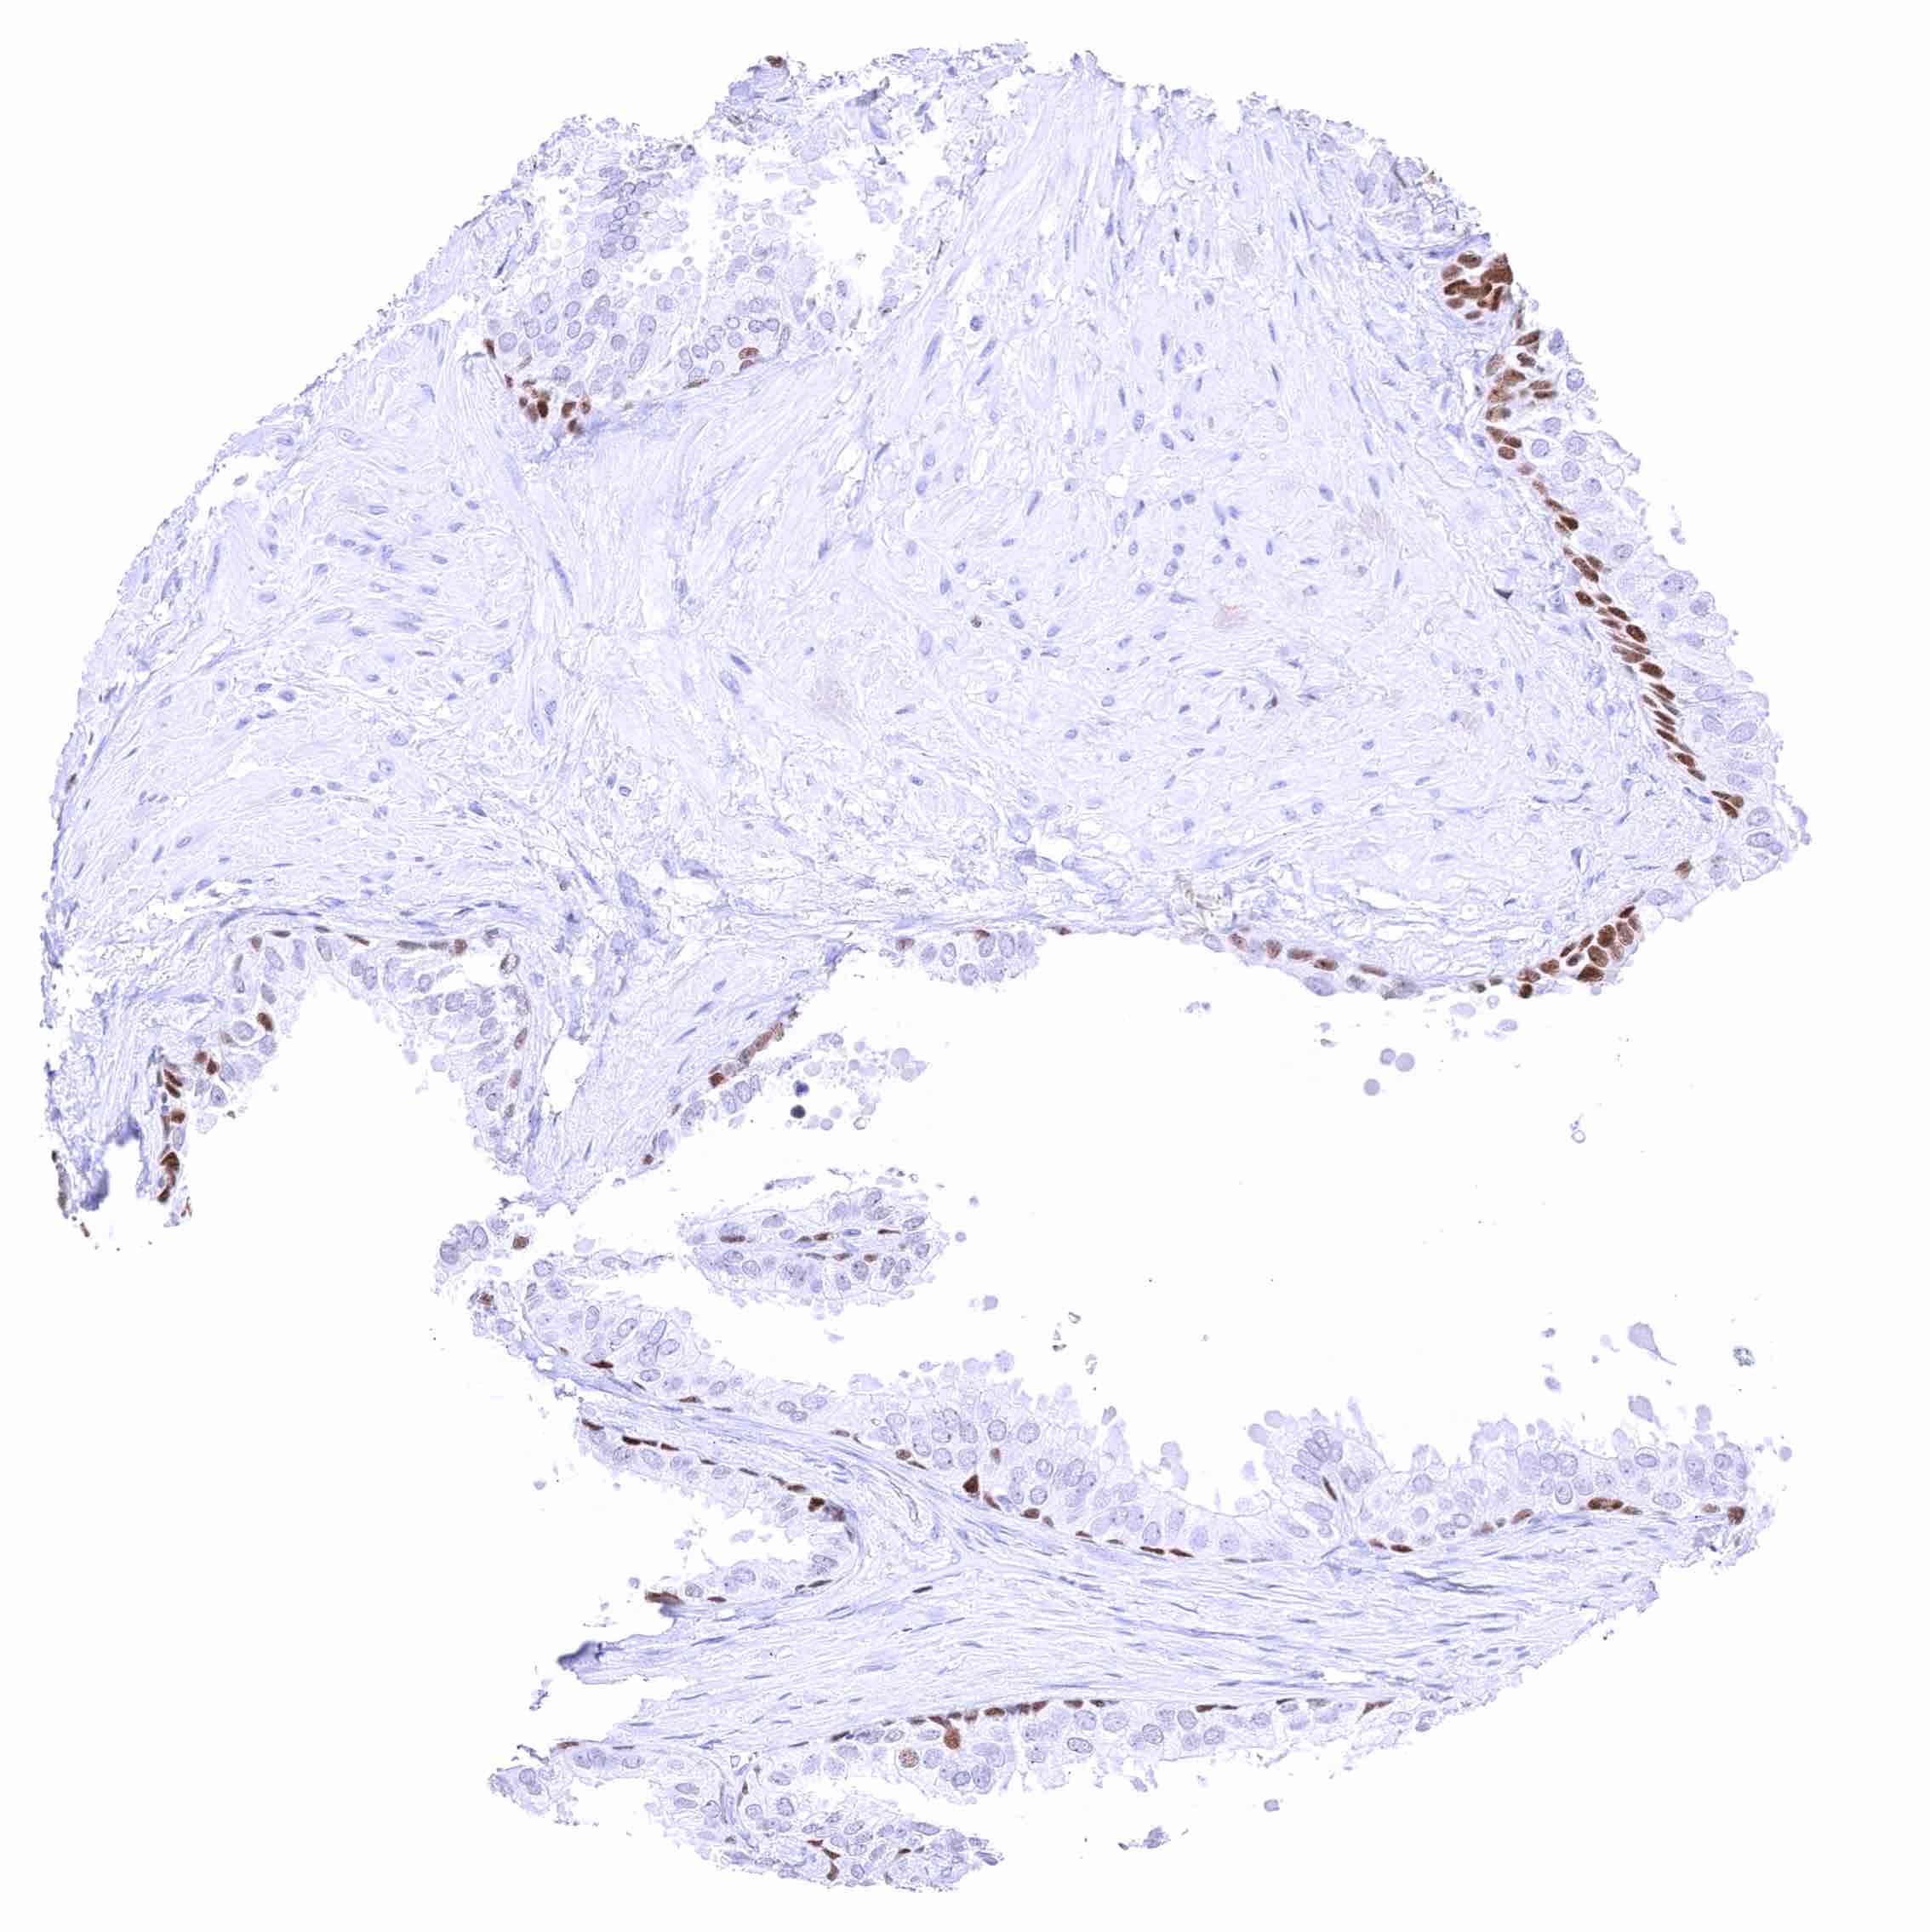

Prostate – Weak to moderate, nuclear GATA3 staining of basal cells. .jpeg